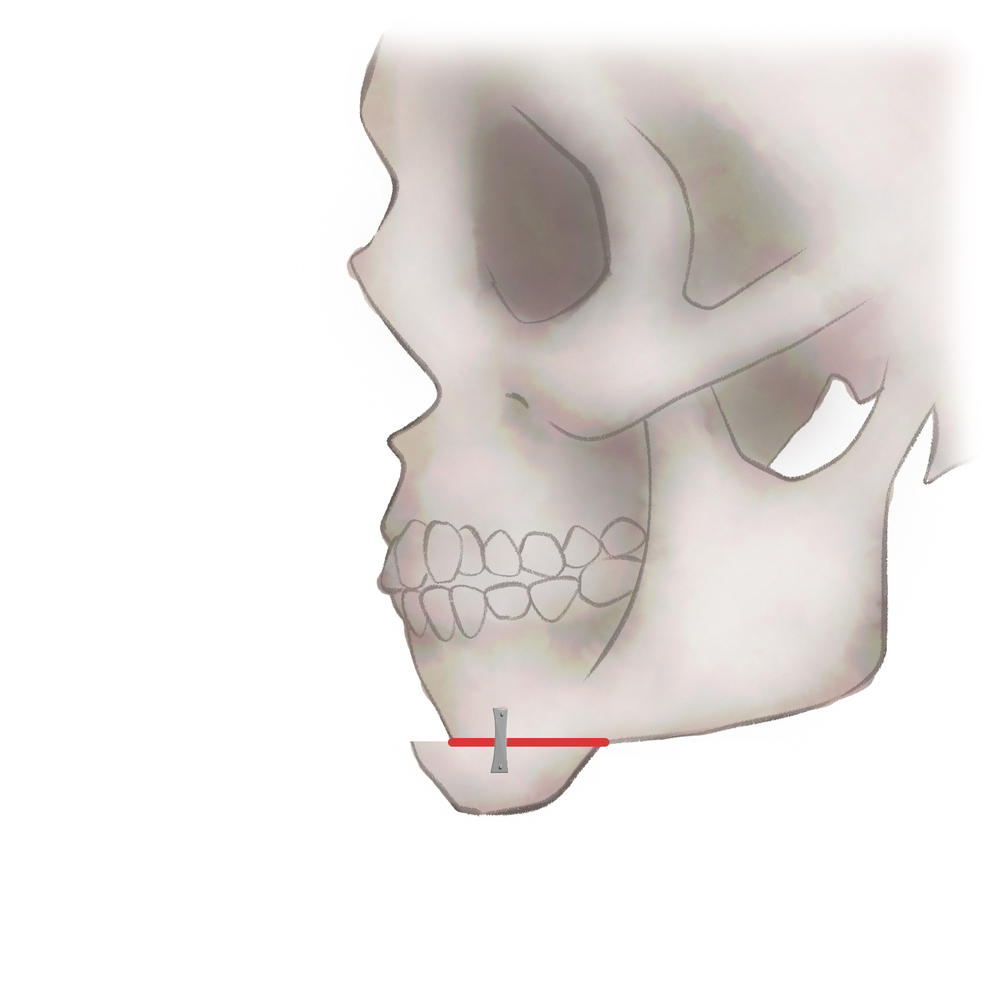

オトガイ骨削り・骨切り

パターン1

骨を切る、もしくは削ります

パターン2

骨を切る、もしくは削ります

パターン3−1

骨を切る、もしくは削ります

パターン3−2

骨を移動してプレートで固定します